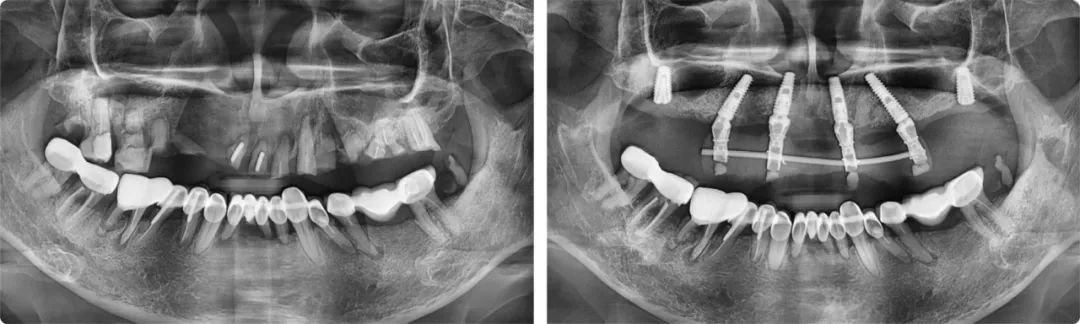

今年五月,叶宏接诊了一位56岁的患者。这位患者的上半口全是牙齿残根,骨量也不好,种植点位非常难选。一般情况下,上颌骨有6-8毫米的高度就可以满足种植条件,但患者只有2-3毫米,风险较大,且种植位置靠近上颌窦,需要采用斜行植体,穿过两个牙位,备孔时要斜着钻,非常考验医生的技术水平和临床经验。

为力求最佳的治疗效果,叶宏为患者制订了个性化的治疗方案。“这例上半口种植由于情况特殊,不能一次性完成六颗牙的种植,我分了两步完成。第一步是即拔即种,种4颗,然后清创,等待恢复,三个月后完成第二步,补种两颗。”

患者术前术后全景片

叶宏解释了这样做的原因:标准的无牙颌种植上颌一般是6-8颗,下颌4-6颗,如果口腔条件允许,他会建议患者至少要种六颗,这样牙槽骨受力更加均匀。如果只种四颗,后期的维护成本相对较高。分两步走的治疗方案虽然麻烦一些,但保障了种植牙的远离稳定性。